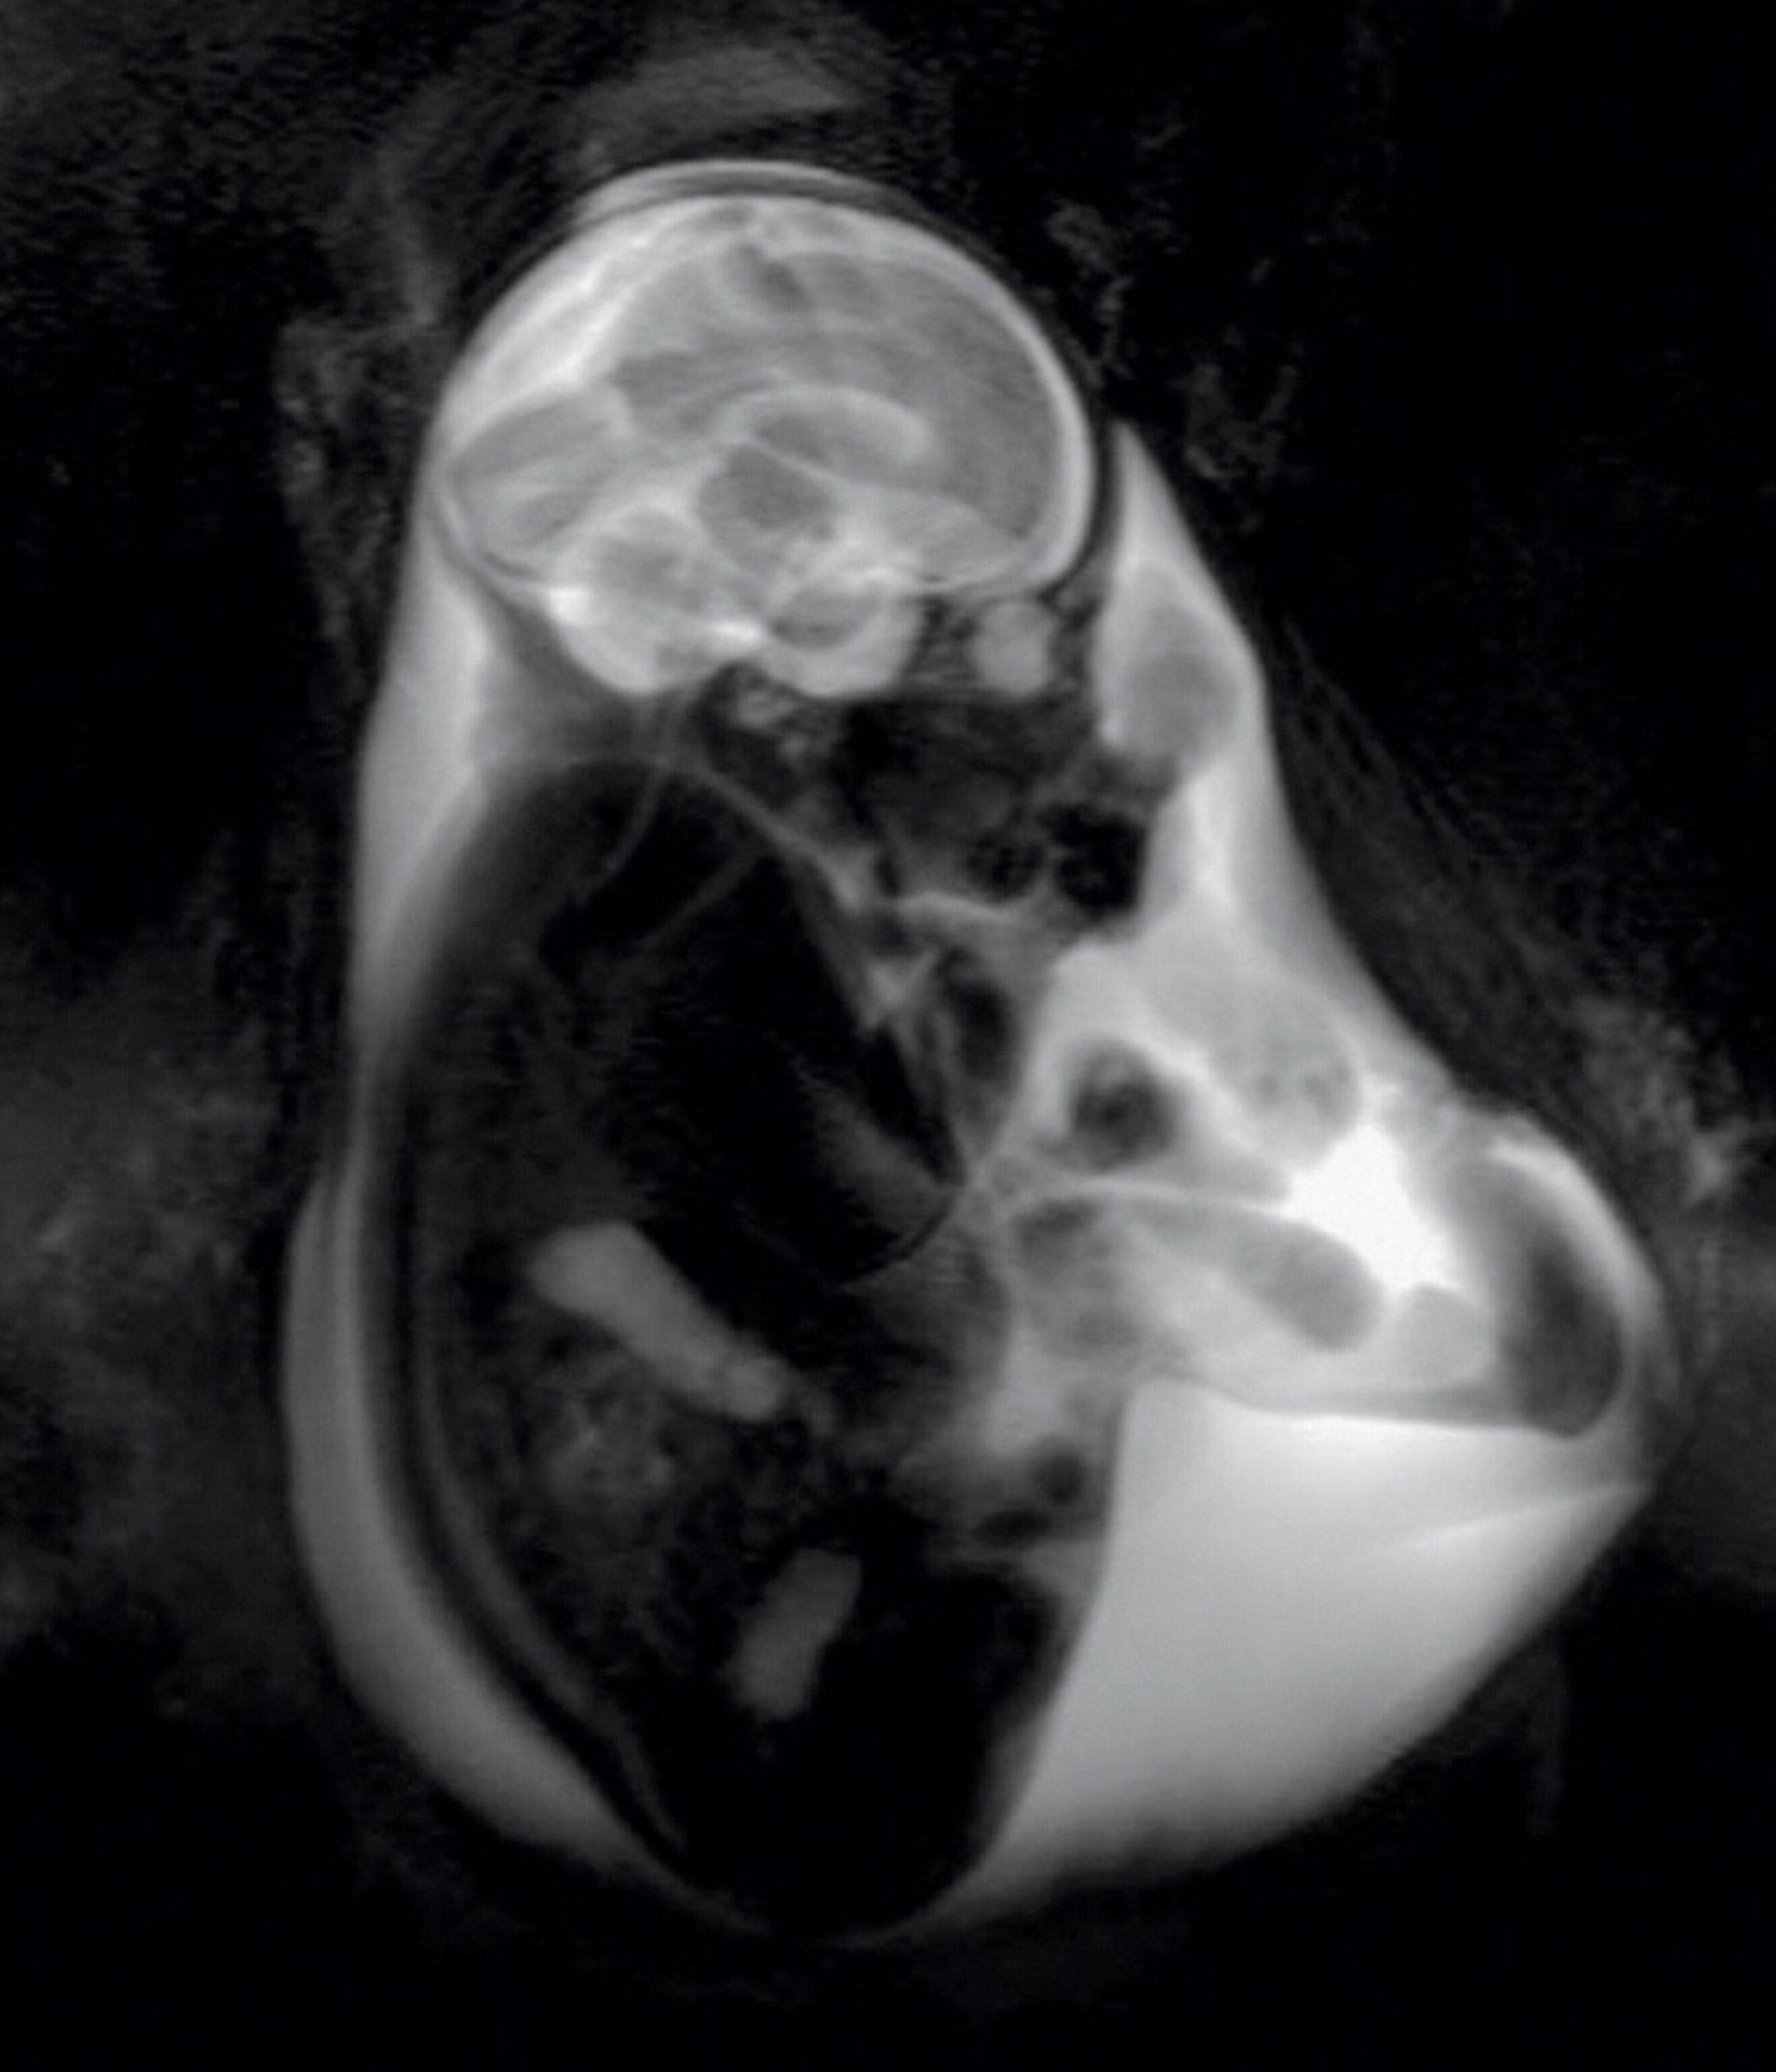

Diagnosis in utero is on the far horizon, says pediatric neuroscientist Moriah Thomason, whose research aims to solve some of the mysteries of the fetal brain. At Detroit’s Wayne State University, she and her team use MRI technology to check the growth of a fetus’s brain and map the neural connectivity within it, creating a groundbreaking snapshot of how well the organ is functioning.

They focus on cases where there’s danger of premature birth, Thomason says, because “we know that preterm children are at higher risk for developmental delays.” Such delays are often blamed on stress or lack of oxygen during birth. Thomason’s work suggests impairment may start in the womb, possibly with an undetected infection.